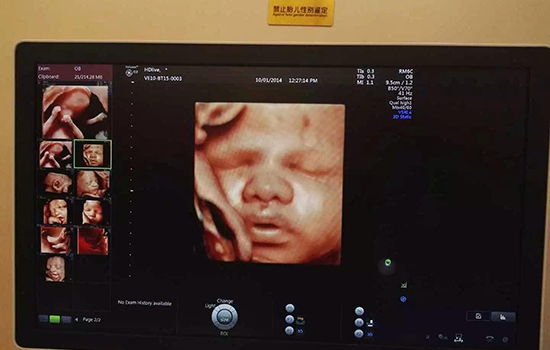

通常情况下,兔唇是能在孕检是被检查出来的。但若在检查时,胎儿用手当着脸面部或者胎儿与母亲对着脸,就看不清胎儿是否兔唇。而且部分胎儿可能受到孕妇本身的身体状况,仪器的性能、医生的个人能力等影响,导致检查不出兔唇。所以有此担忧的孕妈妈在做排畸检查时一定要仔细再仔细!

兔唇的检查是通过B超或是四维彩超检测的,孕期月份越大,检查的结果越准确,像三个月胎儿较小,想检查出兔唇是比较困难的,所以一般在怀孕四个月后才去检查兔唇。而且在整个孕期中孕妇需要做大排畸和小排畸检查,孕妈妈只要跟着检查流程走,一般会及时检查出兔唇的。